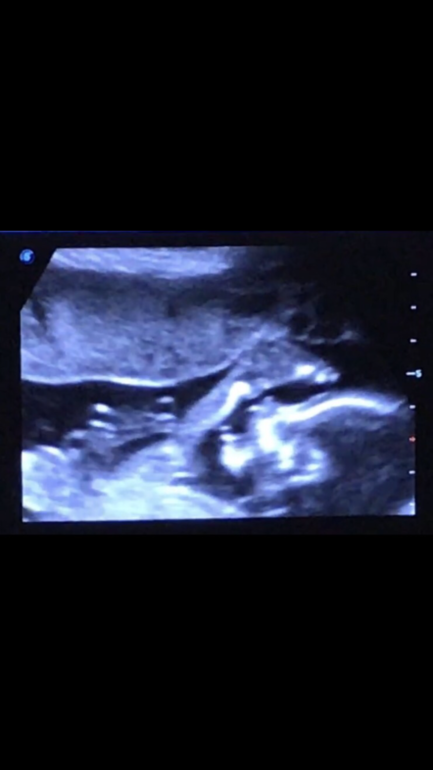

А сынок акробат, вот в такую позу завернулся))) ножки закинул над головой и видимо пытался попробовать их на вкус))😂😂😂